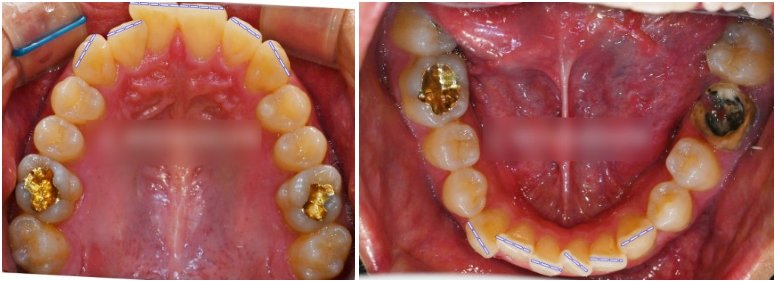

구강 내를 살펴보니,

오른쪽 측절치가 반대 교합 상태였고,

왼쪽 아래 어금니(#36)는

머리 부분이 깨져 치근만 남아 있었습니다.

촬영일 : 23.12.04

치열은 덧니가 심하고 어금니 파절 부위는

시간이 지나며 인접치가 쓰러져

임플란트 를 심기엔 충분하지 않은 공간이

될 수 있기에 공간을 유지해야 됩니다.